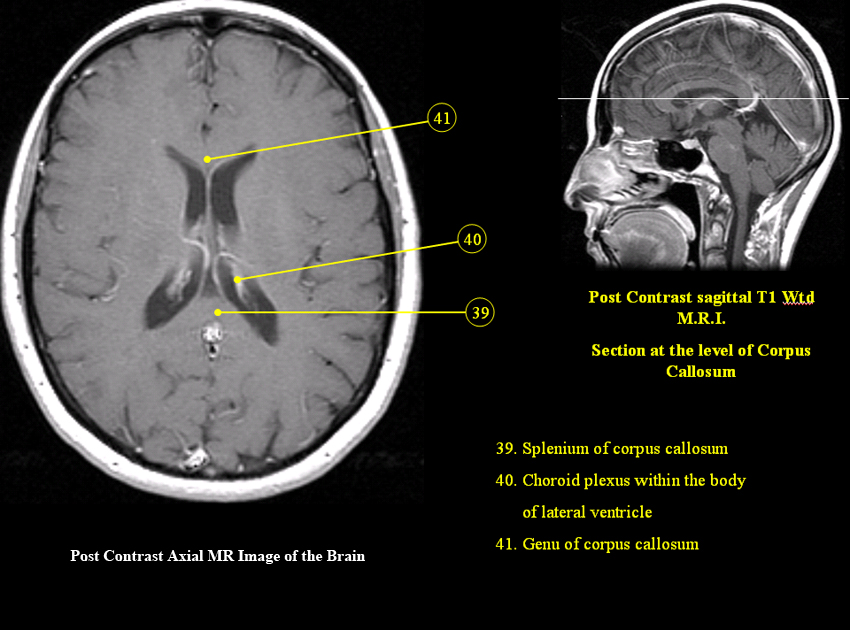

MR Brain and Spine